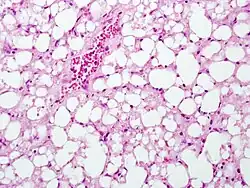

The second phase occurs between 24 hours and 72 hours following overdose and consists of signs of increasing liver damage. In general, damage occurs in liver cells as they metabolize the paracetamol. Hallmark pathology on liver biopsy includes regions of coagulative necrosis in zone 3 of the liver acinus, around the central venules, as these hepatocytes have higher concentrations of cytochrome P450 enzymes compared to zone 1 hepatocytes surrounding the portal venule of the acinus. Remaining viable hepatocyes frequently show ballooning injury and steatosis. [13] The individual may experience right upper quadrant abdominal pain. The increasing liver damage also changes biochemical markers of liver function; International normalized ratio (INR) and the liver transaminases ALT and AST rise to abnormal levels.[14] Acute kidney failure may also occur during this phase, typically caused by either hepatorenal syndrome or multiple organ dysfunction syndrome. In some cases, acute kidney failure may be the primary clinical manifestation of toxicity. In these cases, it has been suggested that the toxic metabolite is produced more in the kidneys than in the liver.[15]